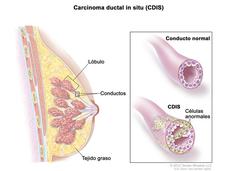

Riesgo de muerte por cáncer de seno es bajo después de diagnóstico de carcinoma ductal in situ

Mujeres diagnosticadas con una afección llamada carcinoma ductal in situ tienen en general un riesgo bajo de morir por cancer de seno, ha indicado un studio.